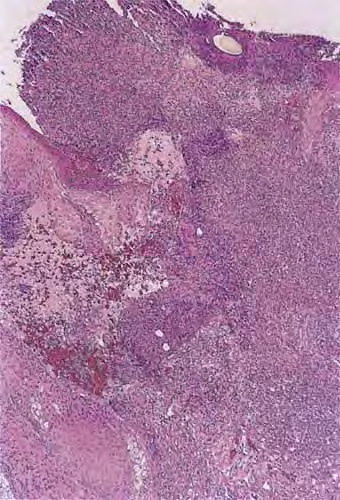

Pathology

The early lesions of HS demonstrate follicular hyperkeratosis. Other dermal features include active folliculitis or abscess, sinus tract formation, fibrosis, and granuloma formation. There is evidence of an inverse relationship between fibrosis and inflammation, supporting the concept that fibrosis corresponds to areas of chronic involvement.68 Histologic feature examination of adnexal structures reveals inflammation of the apocrine glands in only one-third of cases. Interestingly, involvement of eccrine glands (25 percent) has been reported to be more common than apocrine glands (12 percent).103,104 Poral occlusion or cyst formation may be noted. The subcutis may demonstrate some fibrosis, fat necrosis, or inflammation.